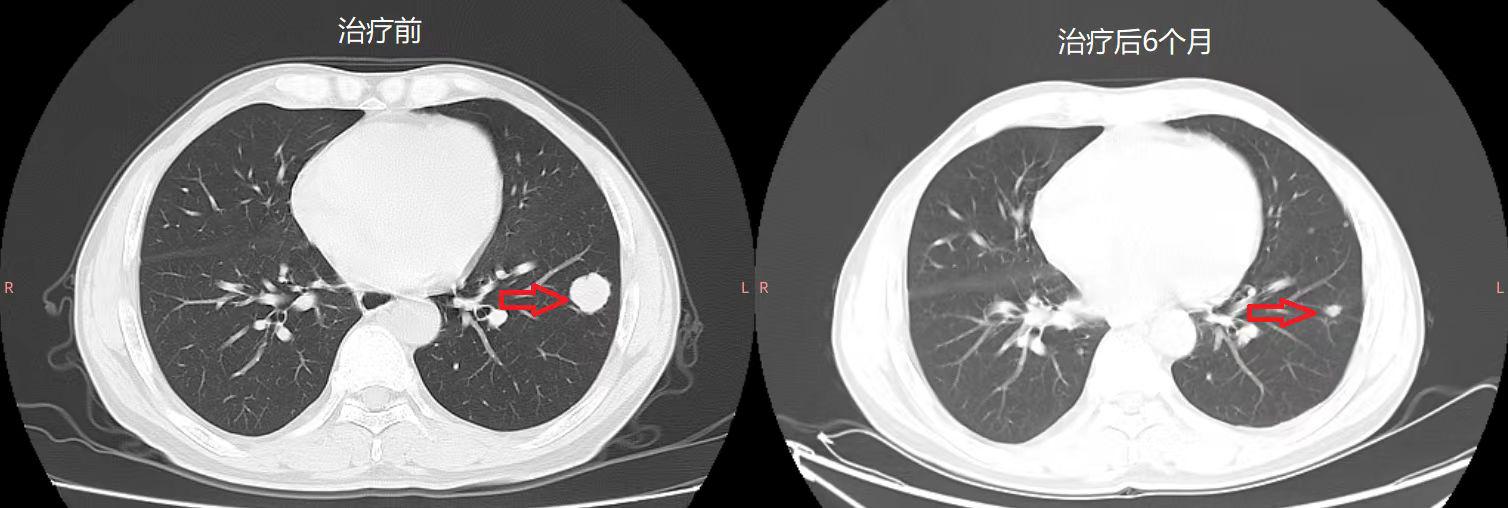

截至目前,共入组13例多线治疗后的晚期结直肠癌患者,并接受了CAR-T治疗,其中10例可评价。这10例患者中,6人病情得到了缓解,2人病情稳定,2人出现了疾病进展,均未出现严重的不良反应事件。其中一名患者在观察的近9个月时间内无任何其它抗肿瘤治疗,肝功能等生化指标有所改善,病情一直稳定无进展,个人生活质量也得到了提高,情绪也有好转。复查的CT结果显示肝和肺转移灶也显著减少,肿瘤缩小的总体积达40%(如下图2)。

图2 肝部和肺部肿瘤缩小情况前后对比图